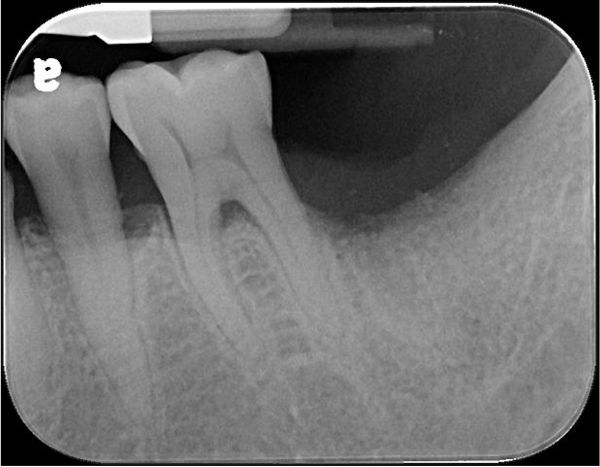

拔牙補骨

6個月追蹤

骨癒合良好